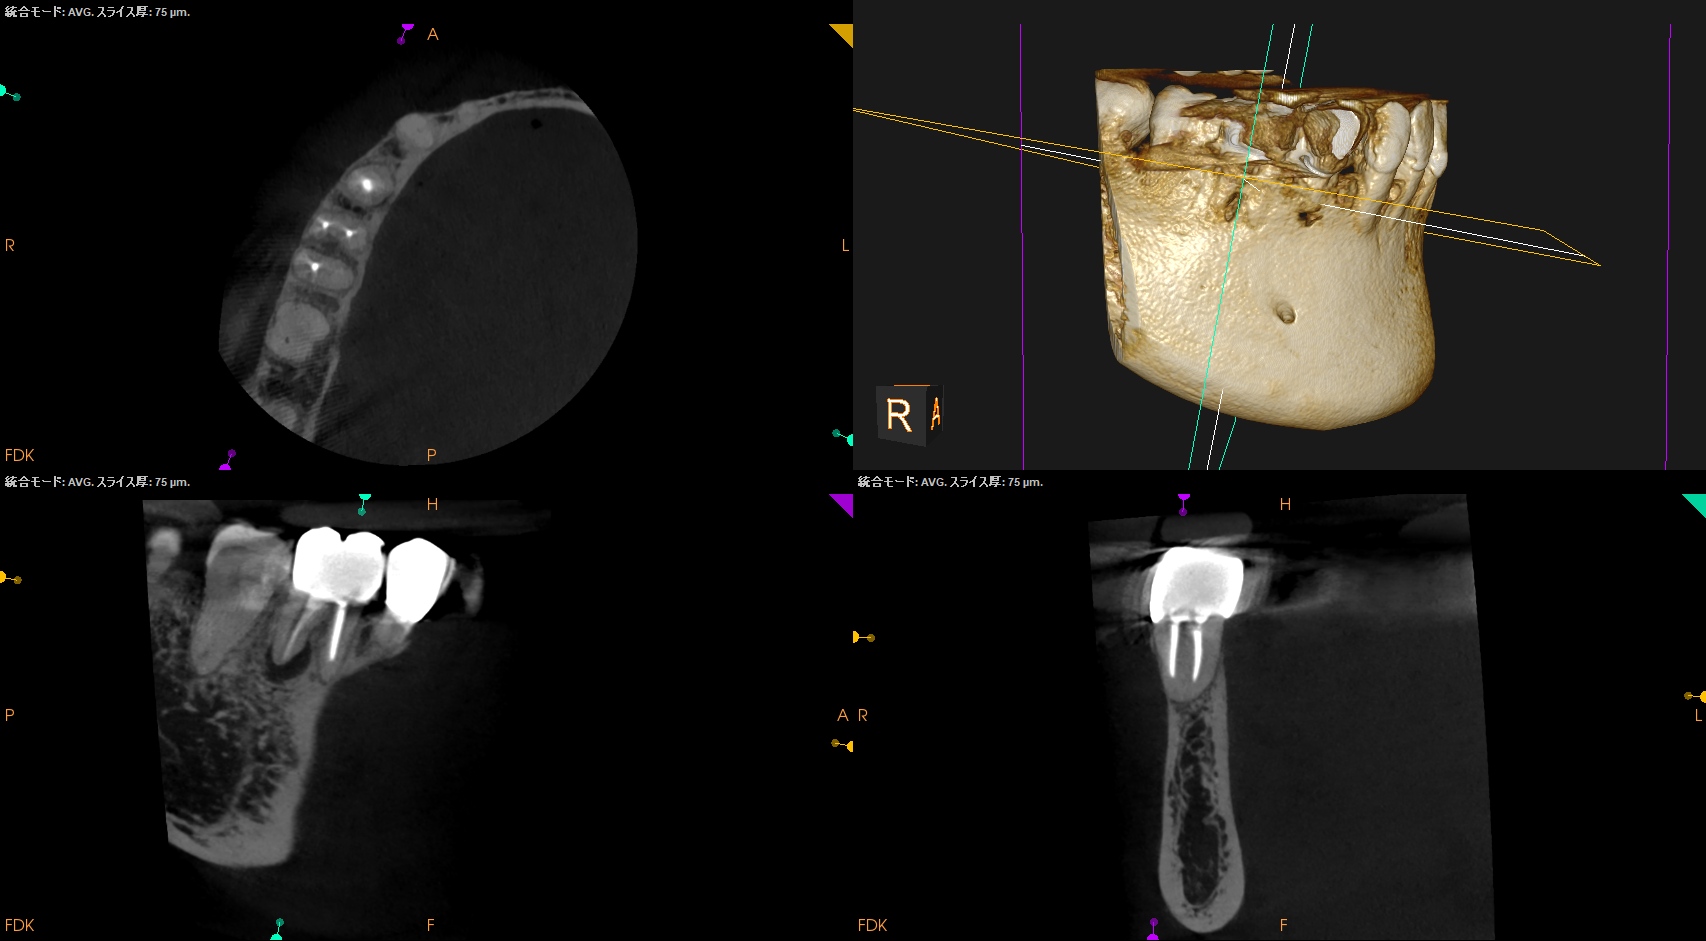

#30 D Apicoectomy(2025.10.8)

OsteotomyしてRoot resectionした。

Retroprepした。ここが一番時間がかかる。

逆根管充填した。

PA, CBCTを撮影した。

問題はないだろう。